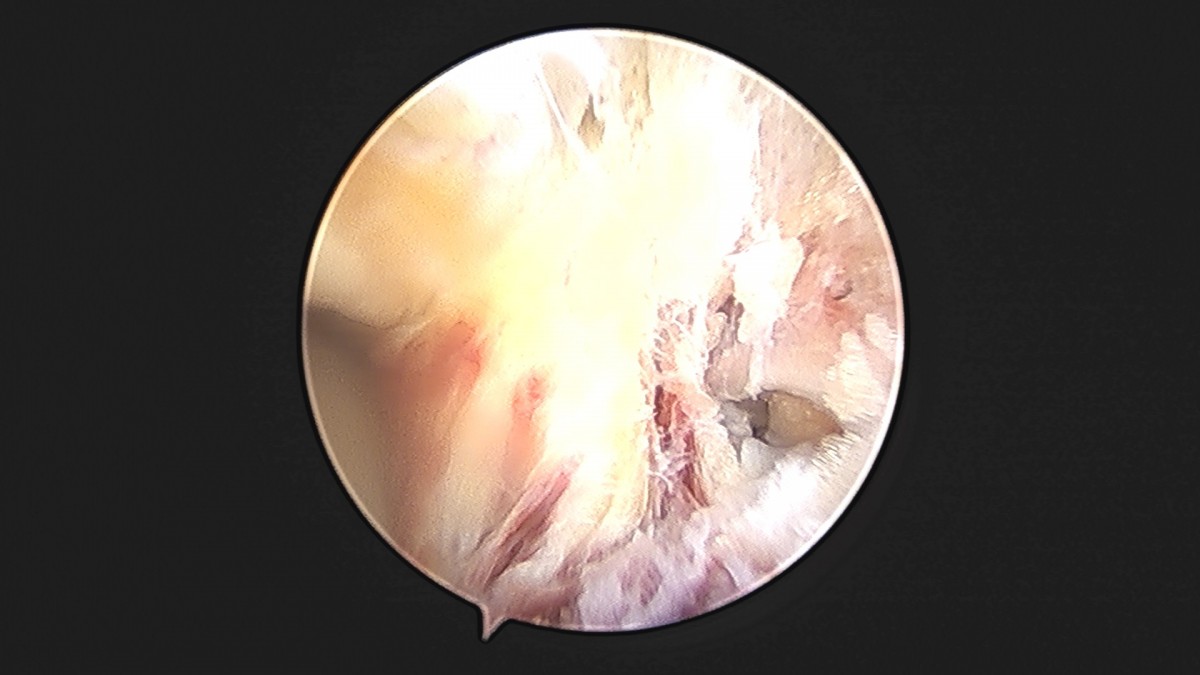

이재상원장님 발목 인대 봉합술 박찬O 환자

dae765e4d9ac96aee867c9d6292d8784_1758007284_4686.jpg